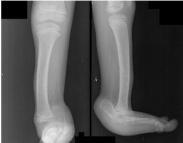

先天性肌缺如(congenital absence of muscles)臨床上比較少見,是由于胎兒本身發(fā)育異常,或因在宮內(nèi)受到機械阻礙所致。常表現(xiàn)為單塊肌肉部分或全部缺如,也可表現(xiàn)為某一組肌肉的缺如。如果缺如的肌肉不能被其他正常肌肉所代償,則可能出現(xiàn)畸形。